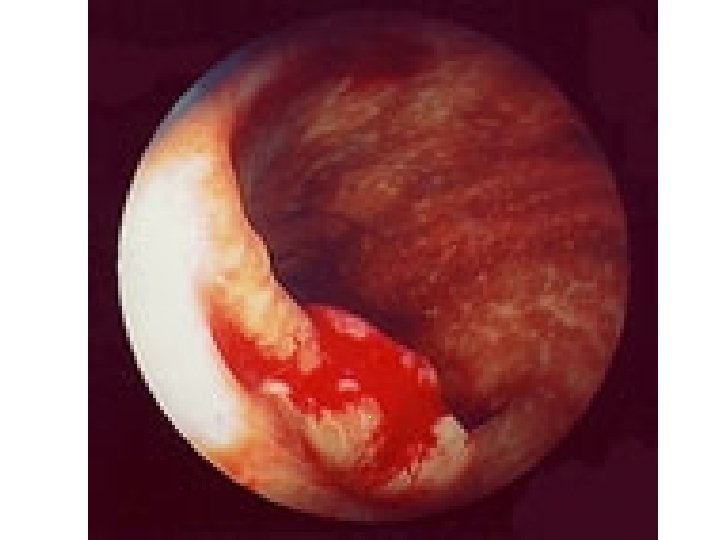

Centrální bronchiální karcinom

Obrovský invazní metastázní bronchiální karcinom

Prorůstající bronchiální karcinom

Bronchiální karcinom